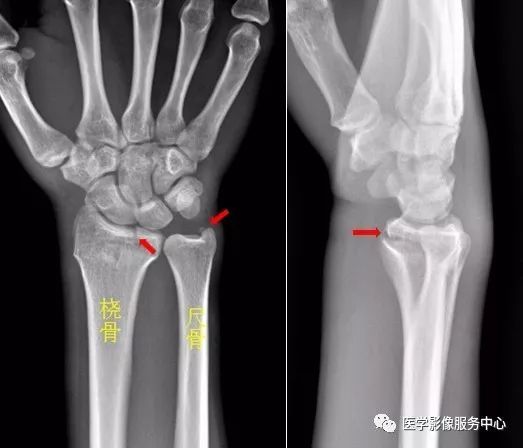

第二章骨 关节系统